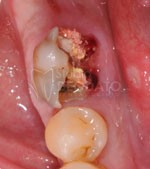

Caso Clinico di impianto post estrattivo